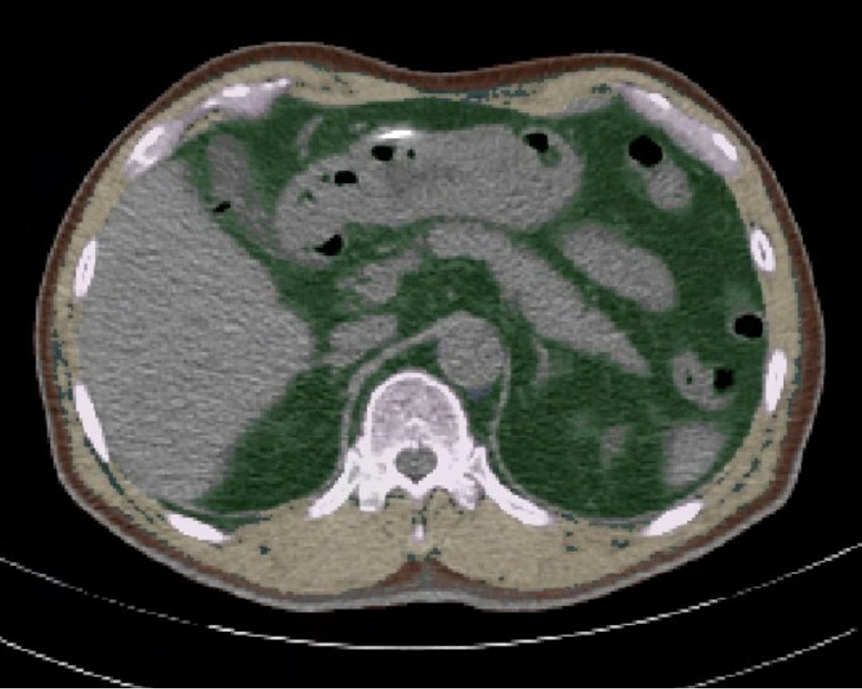

Figure 2

Exemplary cross-sectional images of automated segmentations of subcutaneous adipose tissue (brown), visceral adipose tissue (green), and total skeletal muscle area (yellow) at the T12 level.